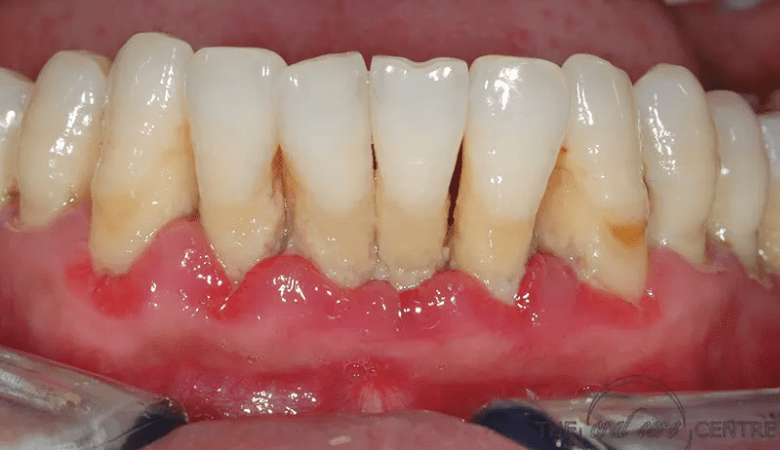

Hình ảnh viêm nướu răng

Chảy máu chân răng khi bị viêm nướu răng (nguồn: Internet)

Viêm nướu răng gây chảy máu chân răng (Nguồn: Internet)